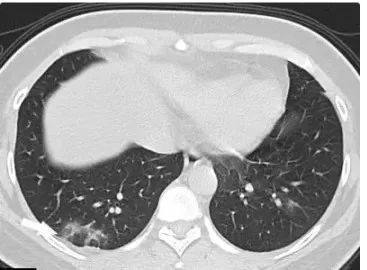

3. COVID-19重症期CT表现

双肺呈弥漫性病变,肺实质广泛渗出、实变,实变影为主,肺结构扭曲,支气管扩张,亚段性肺不张,严重时呈“白肺”。合并少量胸腔积液。

图6 22岁女性,(武汉人员接触史)发热,SARS-CoV-2核酸检测阳性,HRCT示双肺多发实性病灶,左肺下叶片状肺部实变